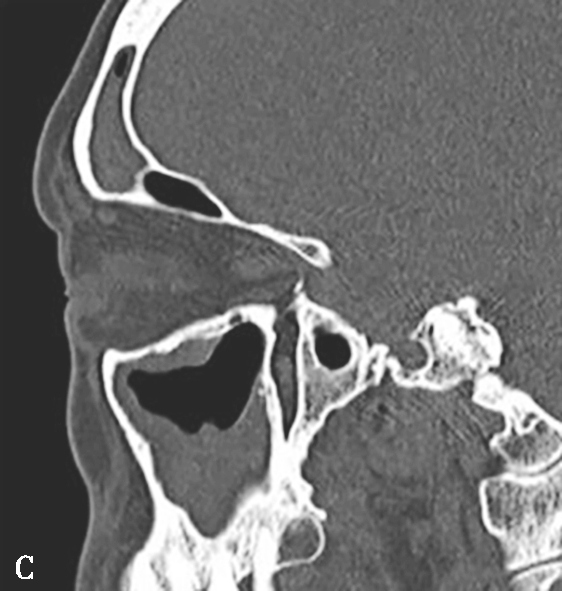

图1-3-20 慢性鼻窦炎

A~C.横断面、冠状面及矢状面CT平扫,示右侧额窦、上颌窦黏膜增厚,窦腔内可见软组织密度影,窦口鼻道复合体狭窄,右侧上颌窦窦壁骨质增生硬化、肥厚;D~F.同一患者横断面MR T 2 WI、T 1 WI及横断面增强T 1 WI,示右侧上颌窦黏膜增厚,呈T 1 WI等信号、T 2 WI高信号影,增强扫描示右侧上颌窦黏膜线样强化